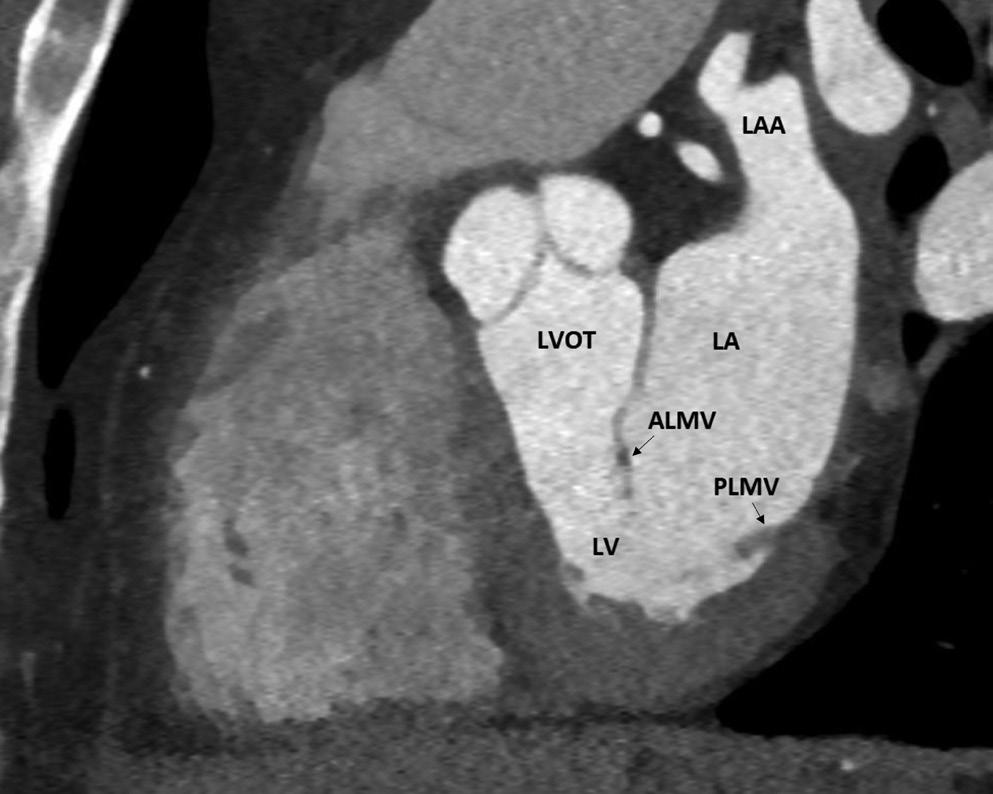

Preprocedural LGE-MRI (1 day before PVI) Post-ablation LGE-MRI (3 months after PVI) LIPV RIPV LSPV RSPV LIPV RIPV LSPV RSPV Postero-anterior view Postero-anterior view

Left: 3D reconstruction of the LA with colour-coding based on image intensity ratios with thresholds for dense scar (red >1.32) and border zone (yellow 1.2–1.32), using ADAS 3D software (Adas3D Medical). Blue lines indicate the plane of the LA slices on the right. Middle: Overlay of the T1-weighted images with the LGE colour-coding described above. White arrows point to local ablation-induced LGE lesions. Right: T1-weighted LGE-MRI slice depicting the LA with evident LGE of PV ostial walls. LA = left atrium; LAA = left atrial appendage; LGE = late gadolinium enhancement; LIPV = left inferior pulmonary vein; LSPV = left superior pulmonary vein; PV = pulmonary vein; PVI = pulmonary vein isolation; RIPV = right inferior pulmonary vein; RSPV = right superior pulmonary vein.